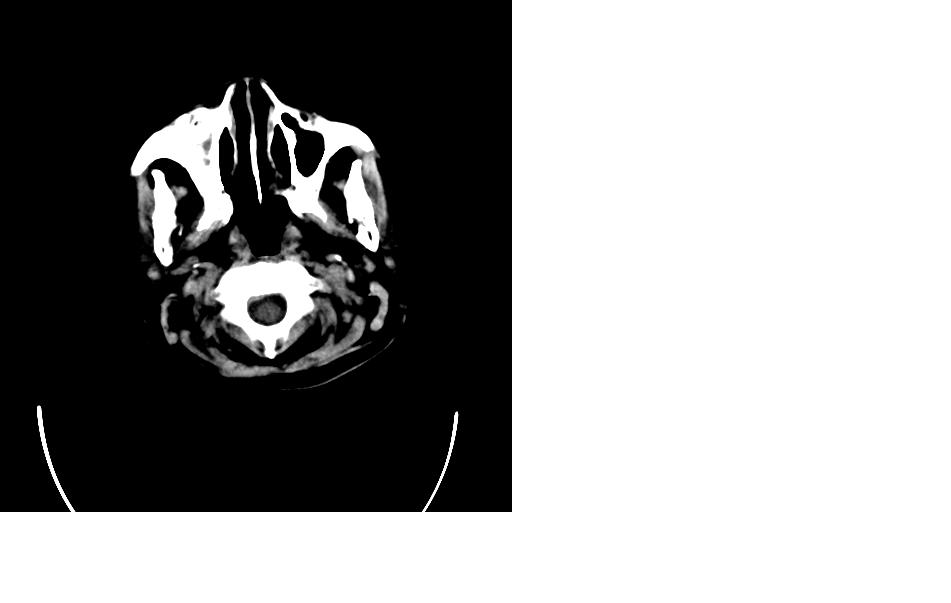

女,77岁,渐进性突眼2年,无其他明显症状

病变位于起源于右侧筛窦,右侧眼球受压移位,右侧大脑半球额叶白质受压塌陷,水肿不明显.额骨呈压迫性骨质吸收变薄.考虑脑膜瘤,建议增强吧

右侧额部软组织密度肿块,界限不清,明显向前下方增长,占位效应明显,内见钙化,局部颅骨明显吸收.考虑:右额叶脑膜瘤.建议:增强

右额窦粘液囊肿,向前累及筛窦并进入眼眶使眼球前突;向下进入颅内右额叶脑质及侧脑室受压

病变应起源于右侧额窦/或额骨板障,肿块周围骨包壳尚完整,呈膨胀挤压改变,右侧眼球受压移位,右侧大脑半球额叶白质受压塌陷,水肿不明显.考虑为良性病变,骨纤维瘤/或骨嗜酸性肉芽肿? 建议增强吧